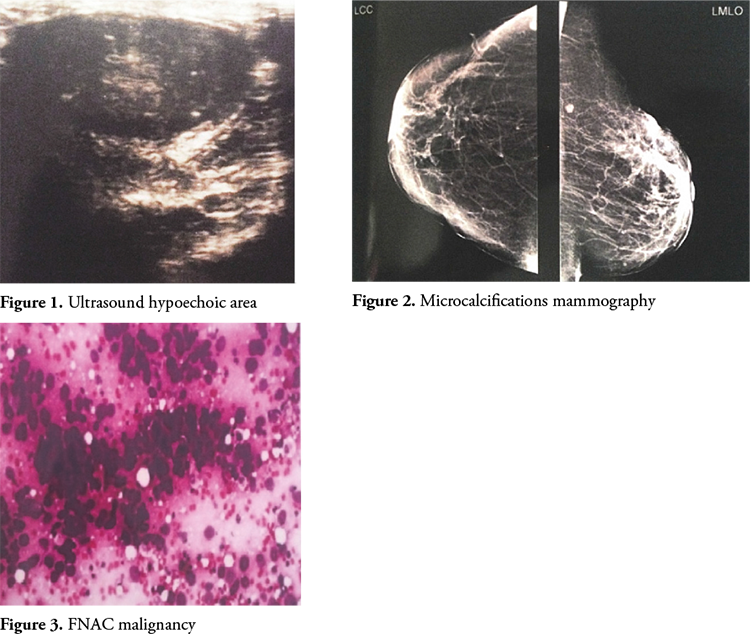

Ultrasonography of the breast suggested 29 cases as benign. Four lumps had features of malignancy on ultrasound. When compared with histopathology for all palpable breast lumps, ultrasound had a sensitivity of 75% and a specificity of 94.12%. The negative predictive value and the positive predictive value were 94.12% and 75% respectively. The diagnostic accuracy of ultrasound for all breast masses was 90.48%. Breast ultrasonography had a concordance value of 90.47%. The p value of USG was 0.005 which is statistically significant.

The sensitivity of mammography for all palpable breast lumps when compared with histopathology in our study was 80% while the specificity was 90.9%. The positive and negative predictive values were 80% and 91% respectively. The diagnostic accuracy of mammography for all breast lumps was 87.5%. The p value of mammography for all breast lumps in our study was 0.006 which is statistically significant. The concordance value of mammography was 87.5%.

FNAC when compared with histopathology for all breast lumps had a sensitivity of 75% and a specificity of 93.3%. The positive predictive value was 75% and a negative predictive value of 93.3% was achieved. The diagnostic accuracy of FNAC in our study was 89.5%. The p value of FNAC was 0.007 which is statistically significant.

The presence of micro calcifications can be detected by X-ray mammography in 30–50% of breast cancers [11]. Micro calcifications on mammography are commonly considered to be the important signs of breast cancer, even though they occur in benign conditions as well. X-ray mammography can be false negative in the setting of a palpable breast lump, to the extent of 4% to 12% [12]. Therefore, malignancy cannot be excluded when mammographic findings of a palpable breast mass are negative. A combination of mammography and continuous ultrasound B-scanning of palpable breast masses improves the diagnostic accuracy obtained with mammography alone and aids in the differentiation of non-diagnostic mammograms [13].

Ultrasound is particularly useful in young women with dense breasts in whom mammograms are difficult to interpret, and in distinguishing cysts from solid lesions. It can also be used to localize impalpable areas of breast pathology. Given a known mammographic location, US with a high-frequency transducer can depict breast masses associated with malignant micro calcifications, particularly clusters larger than 10 mm. US can be used to visualize large clusters of micro calcifications that have a very high suspicion of malignancy [14]. Most palpable masses that are not imaged at all by mammography are detectable by ultrasound [15]. BIRADS score helps interpreting the breast lesions sonographically.